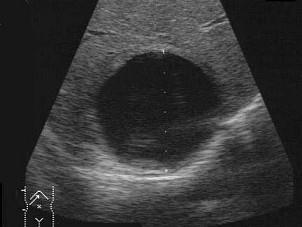

下列图像最可能的诊断是 ( )A.脂肪肝B.肝囊肿C.肝血管瘤D.肝脓肿E.肝炎肝硬化

问题 下列图像最可能的诊断是 ( )

选项 A.脂肪肝 B.肝囊肿 C.肝血管瘤 D.肝脓肿 E.肝炎肝硬化

答案 B